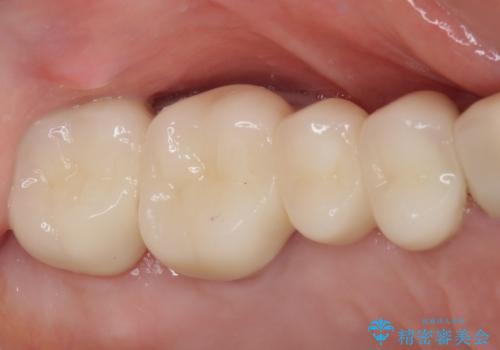

歯肉退縮に対して、上顎からの結合組織移植術(CTG)により、歯根の被覆を行うとともに、歯肉の厚みを増すことで将来の退縮リスクを抑制することとしました。

上顎両側から歯肉を採取したたため、術後は痛みや出血で辛い思いをされましたが、1回の処置で満足のいく結果となりました。